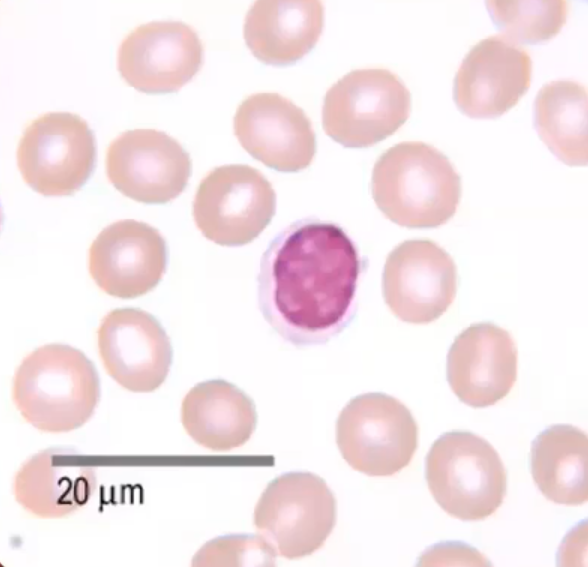

Name

Lymphocyte

Majority nucleus

T cells and B cells